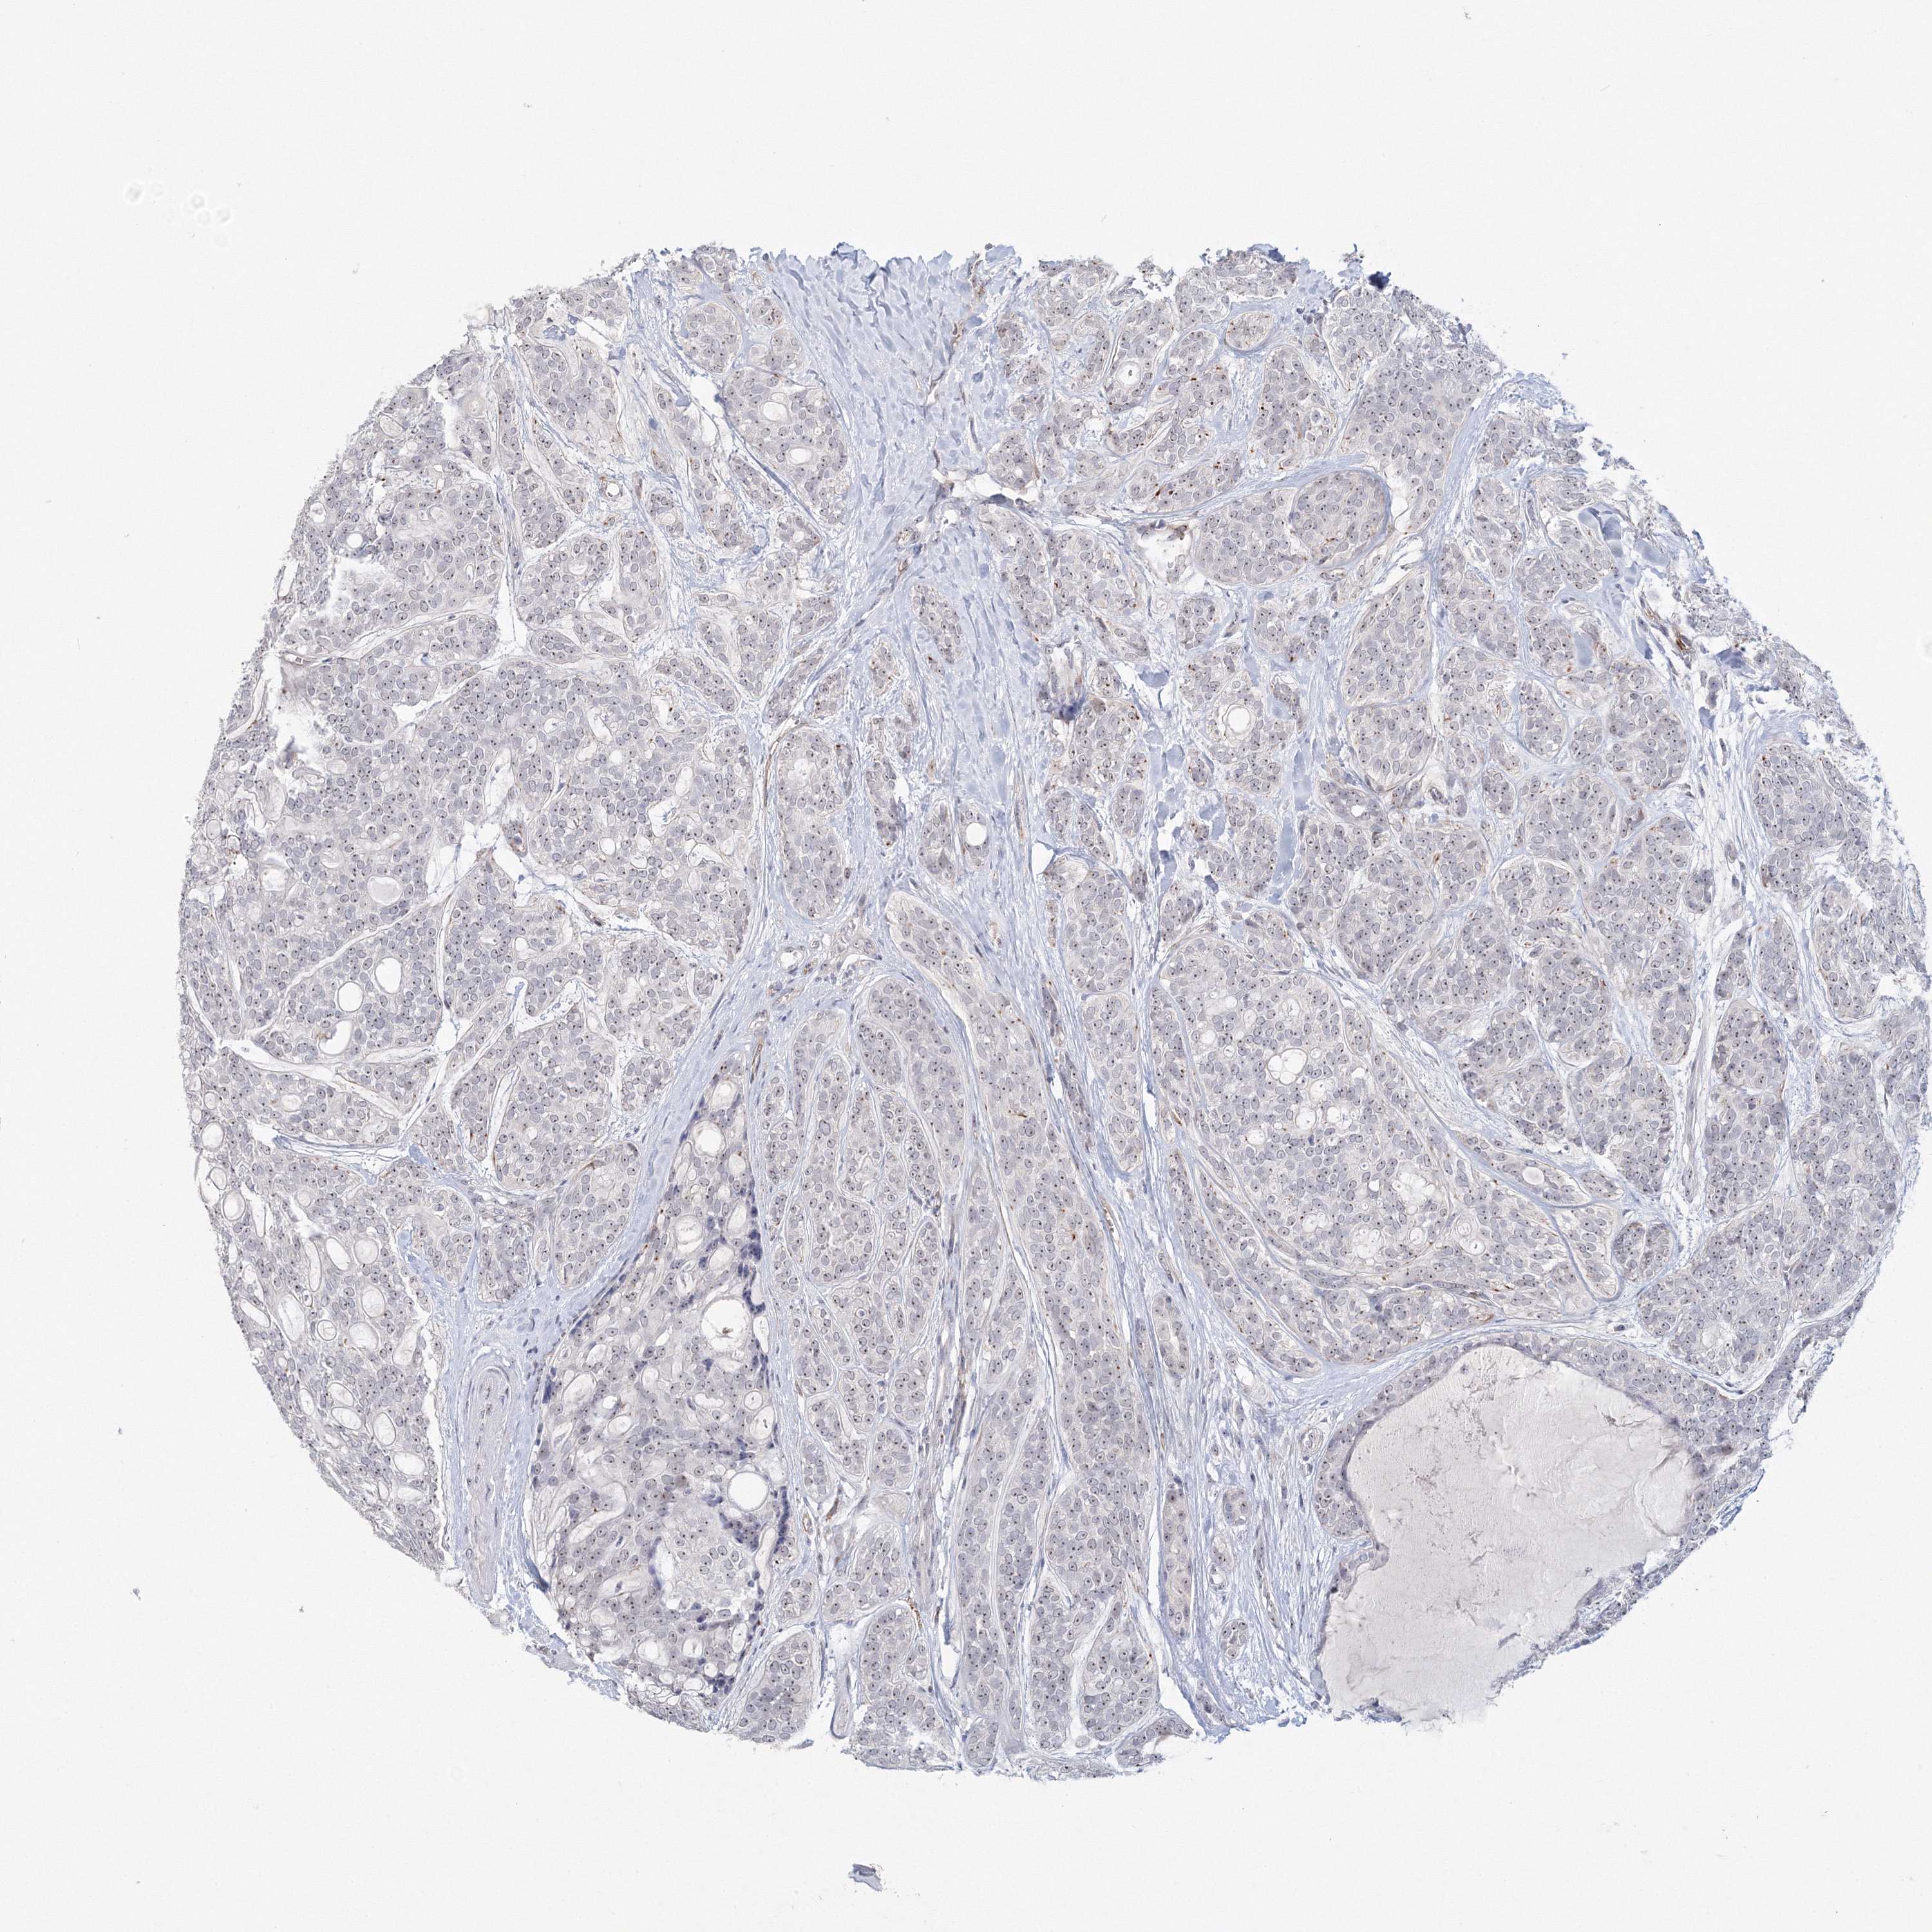

HEAD AND NECK CANCER - Protein expressioni

A mouse-over function shows sample information and annotation data. Click on an image to view it in a full screen mode. Samples can be filtered based on level of antibody staining by selecting one or several of the following categories: high, medium, low and not detected. The assay and annotation is described here.

Antibody stainingi

Antibody staining in the annotated cell types in the current human tissue is reported as not detected, low, medium, or high, based on conventional immunohistochemistry profiling in selected tissues. This score is based on the combination of the staining intensity and fraction of stained cells.

Each image is clickable and will lead to virtual microscopy that enables deeper exploration of all samples and also displays staining intensity scores, fraction scores and subcellular localization as well as patient and tissue information for each sample.

Antibody HPA053669

Antibody CAB037261

Squamous cell carcinoma, NOS

Squamous cell carcinoma, metastatic, NOS